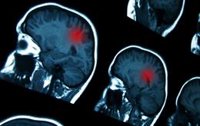

Las patologías del cerebro son una de las principales causas de discapacidad y mortalidad en España

En España, 7 millones de ciudadanos padecen algún tipo de enfermedad neurológica, siendo el ictus la segunda causa de mortalidad en el país. Además, 9 de las 15 patologías más frecuentes en España son neurológicas, siendo el ictus, el Alzheimer, el Parkinson y la Esclerosis Lateral Amiotrófica (ELA), las más frecuentes.